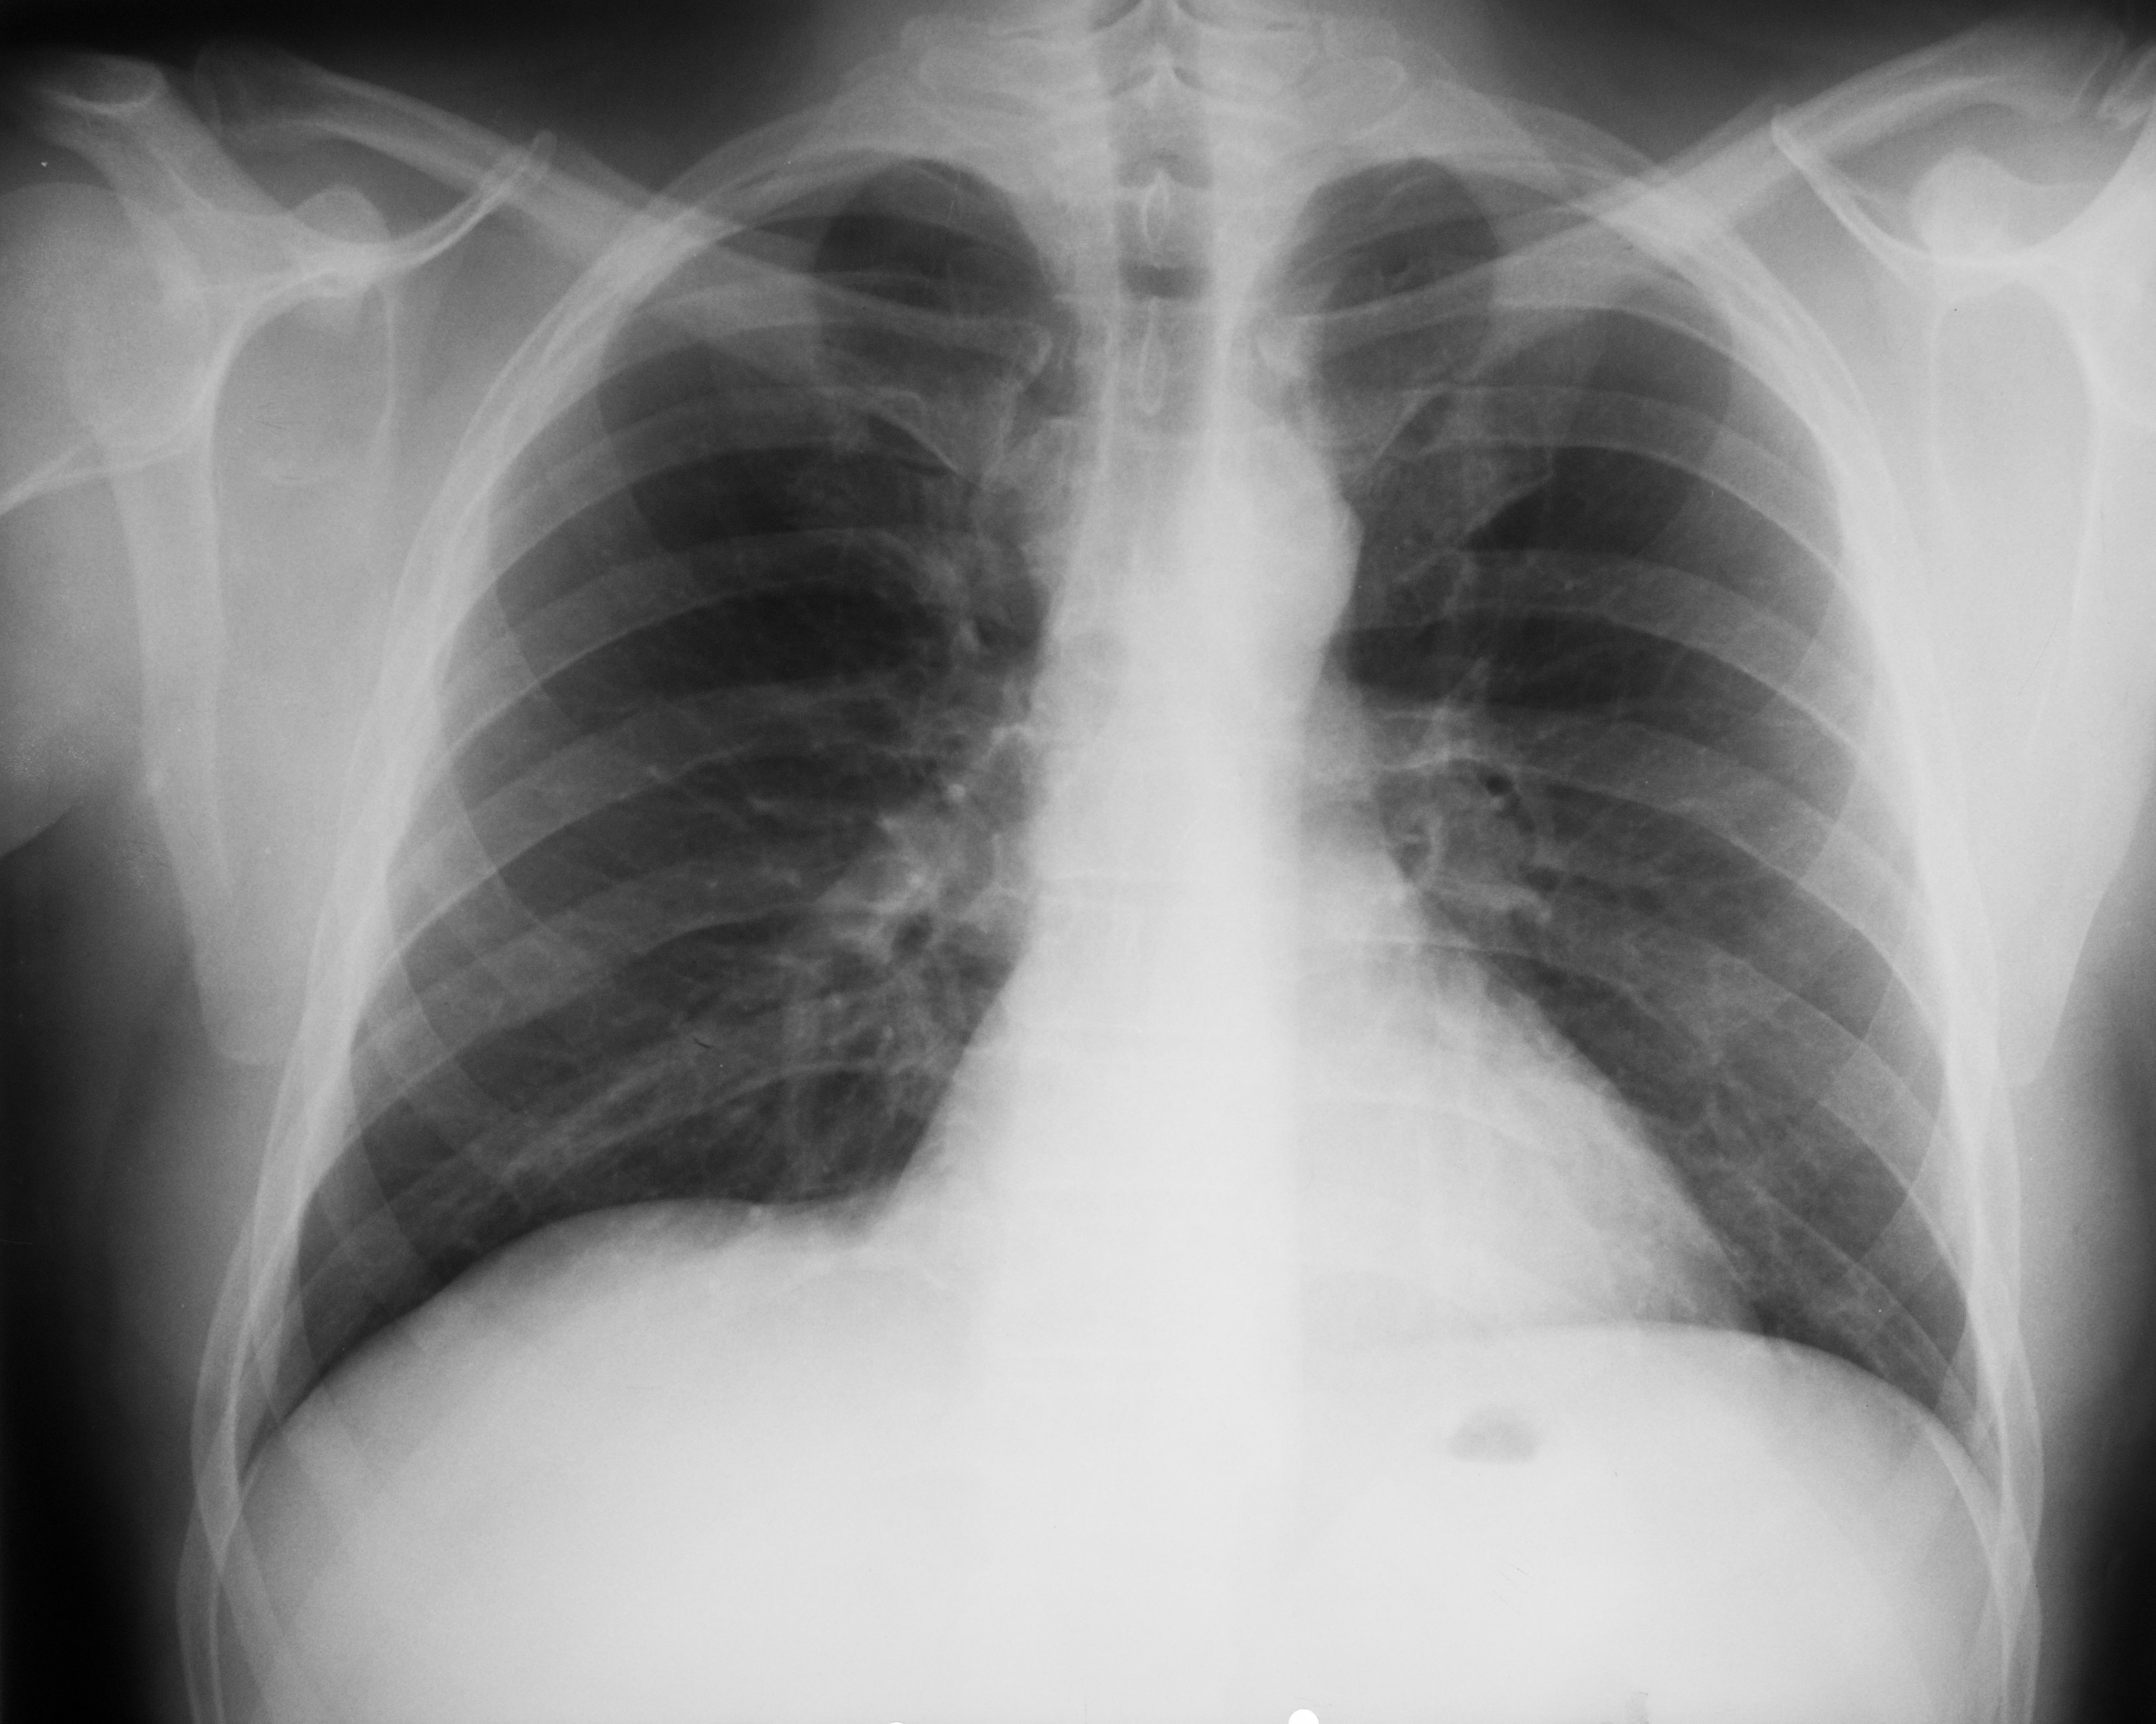

Rx toraco-mediastino-pleuro-pulmonară,incidența de față – vedem o imagine toracică normală (ITN) cu desen pulmonar,cu hil,fara nicio modificare patologică